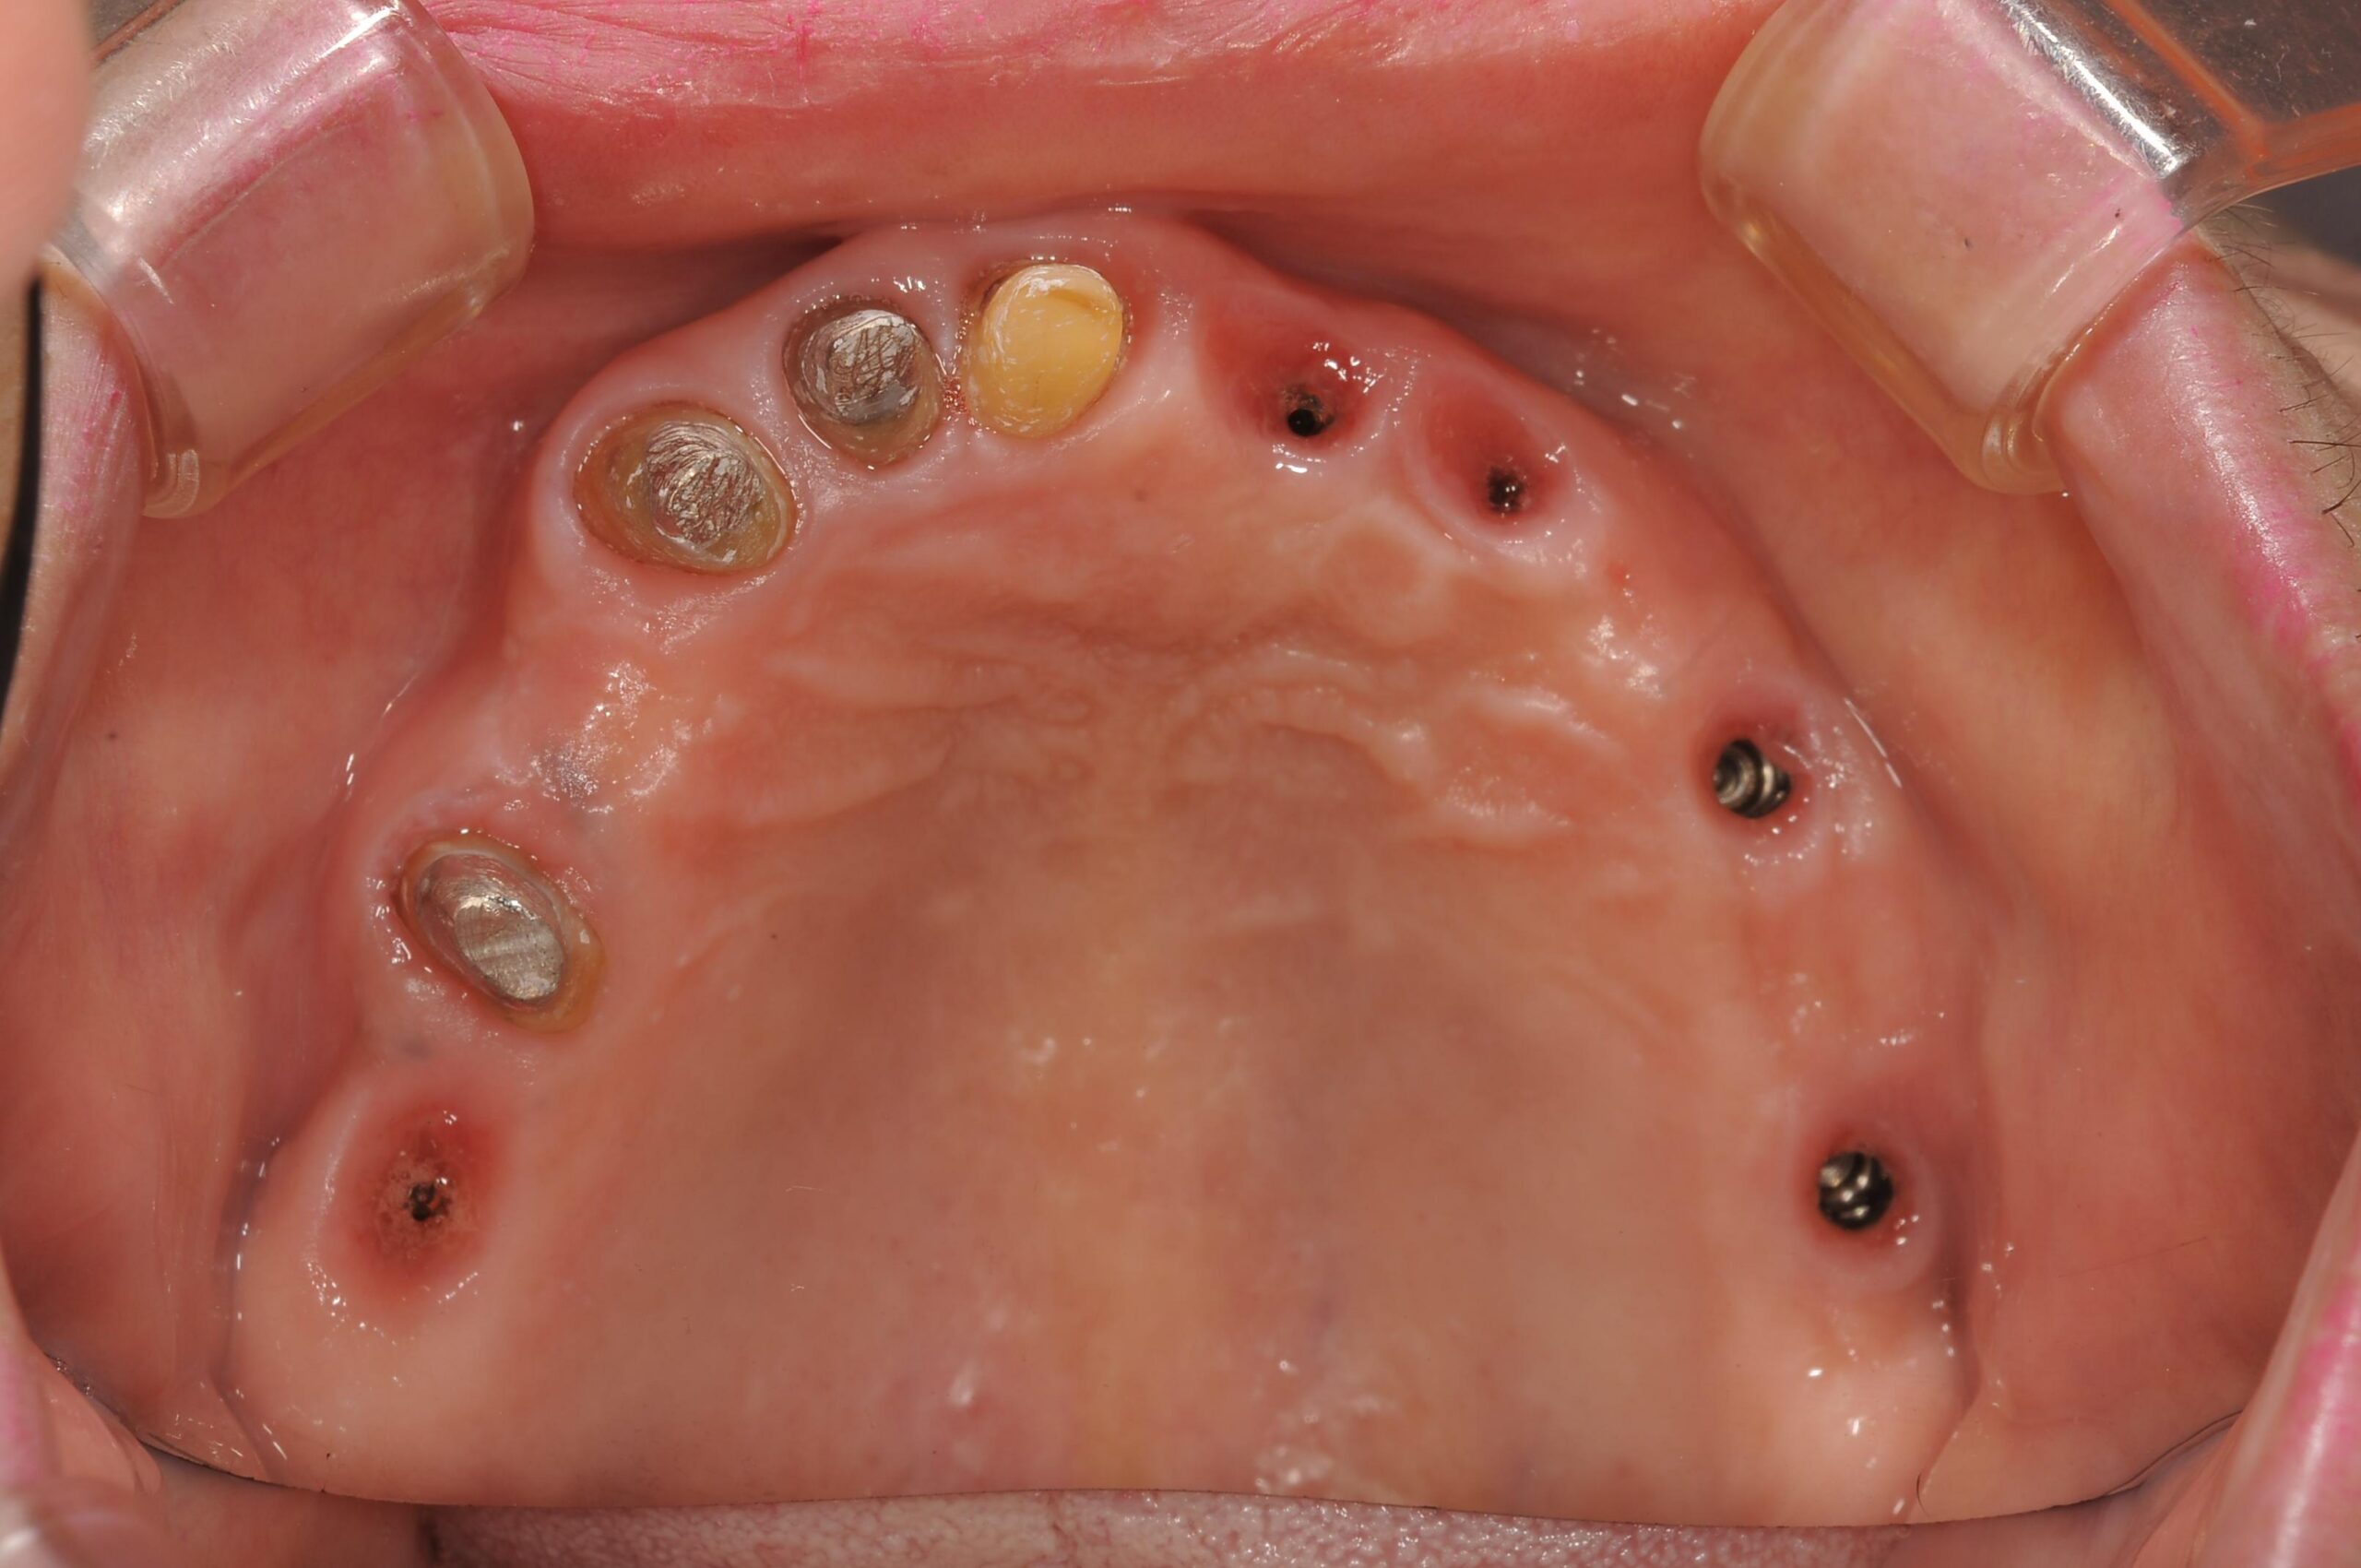

下顎両側に3本ずつ、上顎に5本のボーンレベルインプラントを埋入しましたが、すべてのインプラントをあらかじめコンピューター上で3次元的に埋入位置を決定し、その位置へ確実に埋入できるようにサージカルステントを用いるガイデッドサージェリーという手術方法を用いて行いました。

また、粘膜の中の骨の形が3次元的にわかっているので、歯ぐきを切開せずに埋入することも出来ます(フラップレス埋入)。

ガイデッドサージェリーに使用するサージカルガイドです。 ドイツのシーキャット社で作製されます。